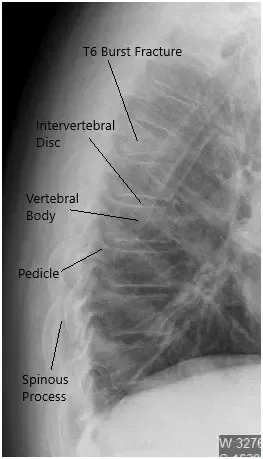

Radiografía preoperatoria de la columna toracolumbar en vista lateral.

Se presentó en urgencias del hospital con un dolor insoportable. Un examen de imagen reveló una fractura explosiva del cuerpo vertebral T6 con más del 50% de pérdida de altura y angulación aguda en ese nivel, que empeoró con la flexión y la extensión.

La TC reveló fractura aguda moderada por compresión de cuña asociada al cuerpo vertebral T6. La corteza posterior del cuerpo vertebral T6 se imprime ligeramente sobre el margen anterior del saco dural torácico. El hematoma mínimo se sitúa entre el cuerpo vertebral T6 y la pleura circundante.